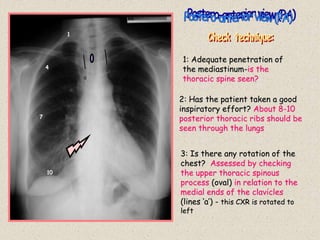

3: Is there any rotation of the

chest? Assessed by checking

the upper thoracic spinous

process (oval) in relation to the

medial ends of the clavicles

(lines ‘a’) - this CXR is rotated to

left

1

4

7

10

a

1: Adequate penetration of

the mediastinum-is the

thoracic spine seen?

2: Has the patient taken a good

inspiratory effort? About 8-10

posterior thoracic ribs should be

seen through the lungs